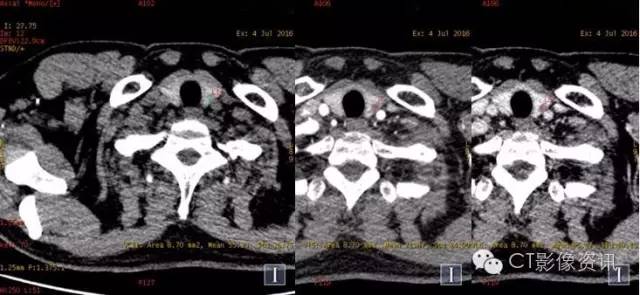

常规平扫及强化两期

平扫及强化两期碘基图

常规图像及碘基图显示病灶轻度强化。